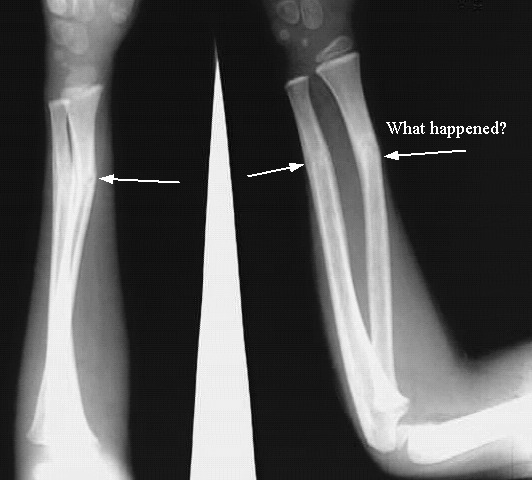

Upper Limbs:Radius & Ulna Fracture:

Arrows: Fractured Lower shafts of Radius & Ulna.